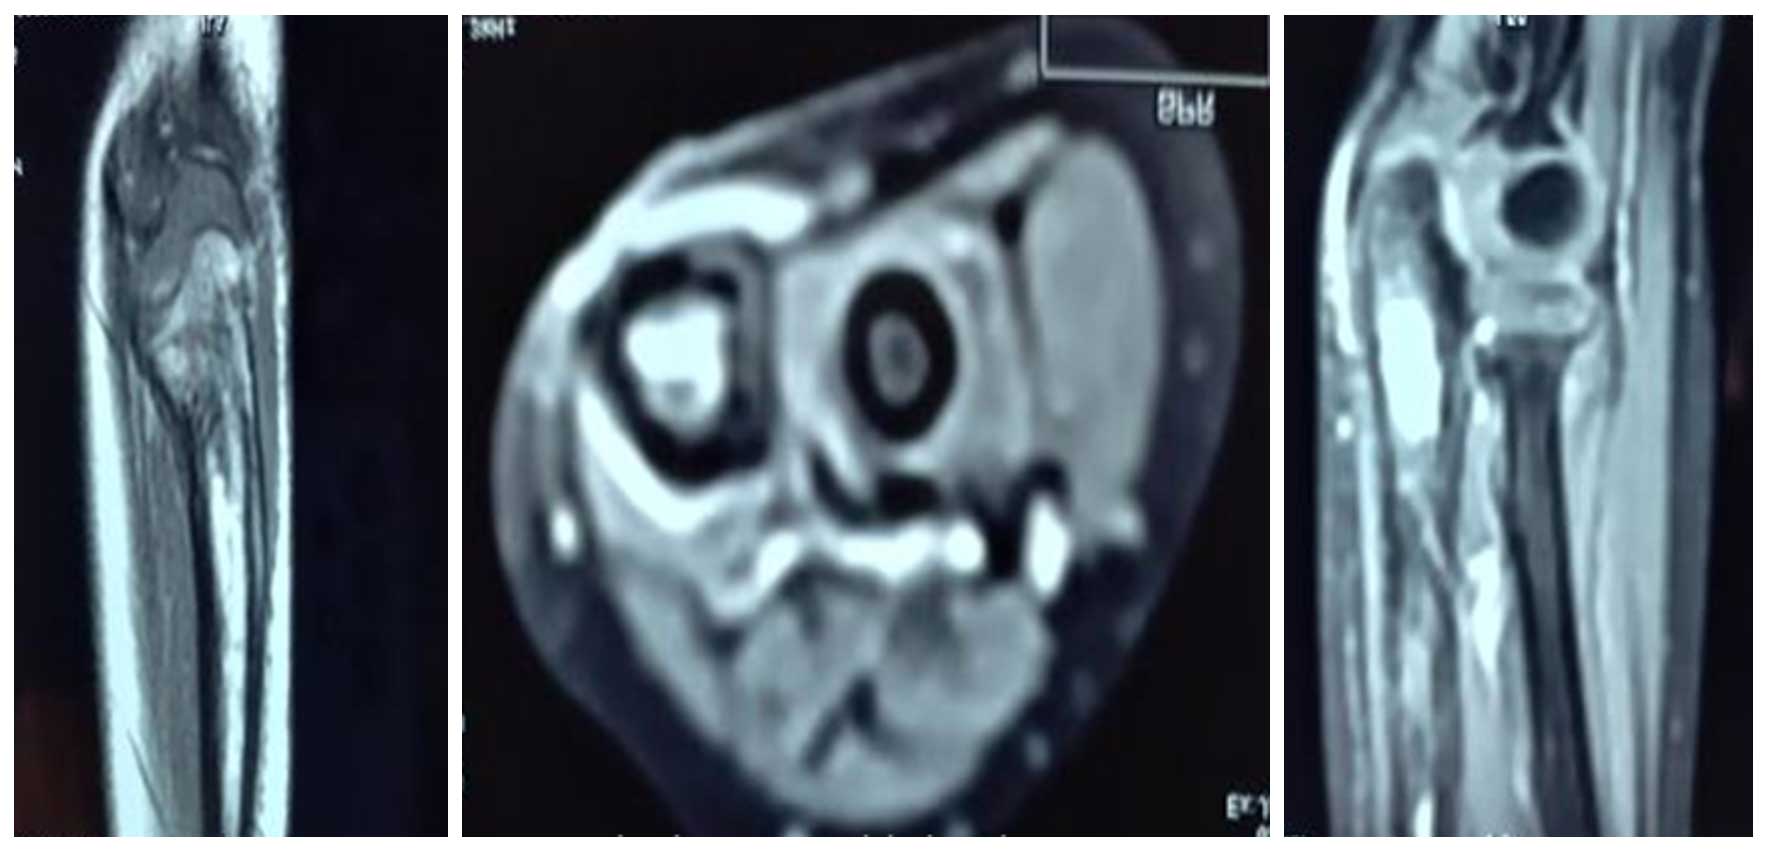

Ameliyat Öncesi: MR’da aynı lokalizasyonda düzensizlik, periost reaksiyonu ve peritümöral ödem görülmekte .